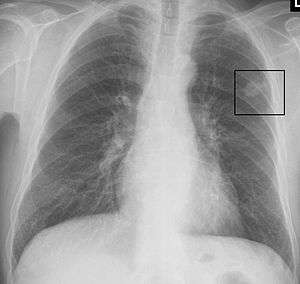

Most cancers are initially recognized either because of the appearance of signs or symptoms or through screening. Neither of these lead to a definitive diagnosis, which requires the examination of a tissue sample by a pathologist. People with suspected cancer are investigated with medical tests. These commonly include blood tests, X-rays, CT scans and endoscopy.